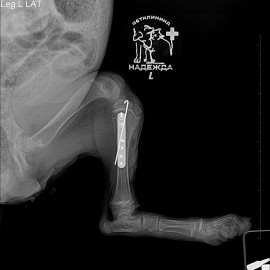

После проведенных исследований был поставлен диагноз: перелом левой голени.

Проведена операция: остеосинтез левой голени.

Снимки 2-3 после операции.